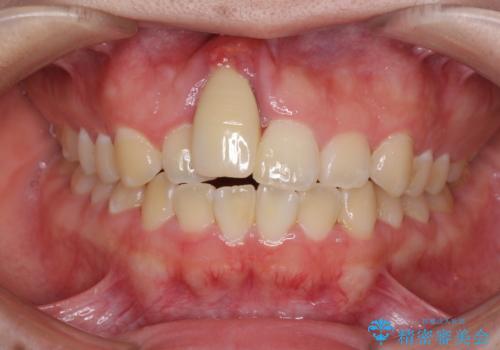

歯列全体のクロスバイトを治したい ワイヤー装置による矯正治療

- 上下のデコボコと前歯のクロスバイトを改善したいとのことで来院された患者様です。

マウスピース矯正での自己管理には自信がないとのことで、ワイヤー装置による矯正治療を行うこととしました。

デコボコの程度は強かったのですが、口元の突出感はなかったため、非抜歯矯正としました。

クロスバイトは、治療の過程で咬み合わせが大きく変化する期間があり、食事が取りにくくなってしまいます。

また、装置が対合歯と咬み合ってしまい、頻繁に脱落するなど、色々と面倒なことがあり、治療がスムーズに進まないことがあります。